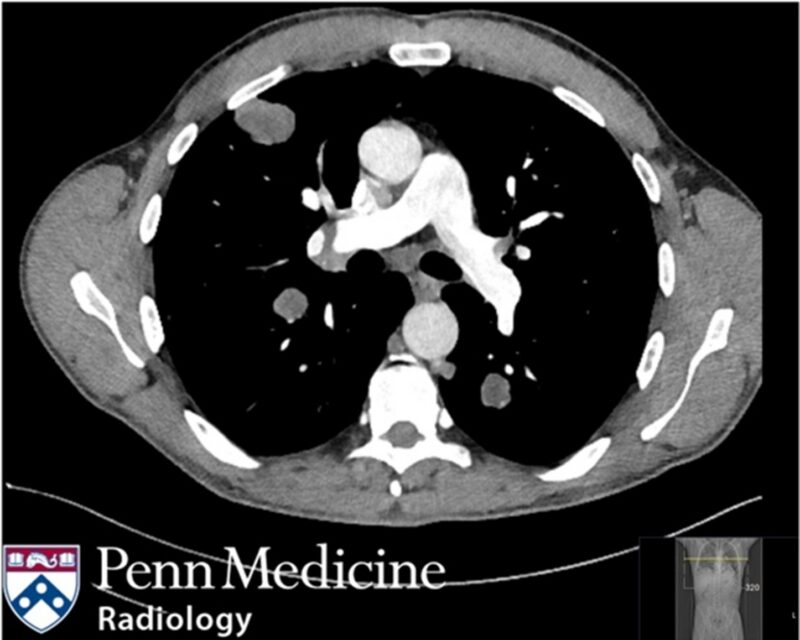

A man in his 60s, previously active in golf and pickleball, presented with difficulty standing, worsening leg weakness, paresthesias, radiating back pain, constipation, and urinary retention.